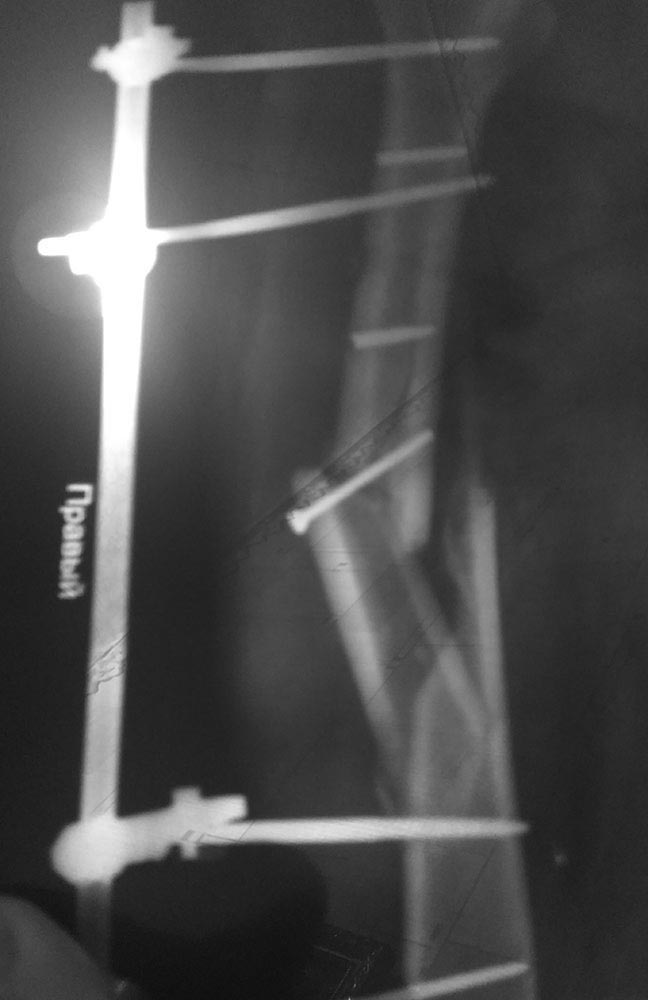

Вчера прислал свежий рентген. Посмотрите пожалуйста.

Также прилагаю снимки сделанные два месяца раннее.

Такое положение было бы как-то приемлемо в ближайшие 2-3 недели после травмы. Почему в течение первого месяца не был выполнен переход с временной наружной фиксации на окончательную внутреннюю? Или хотя бы аппарат Илизарова?

Неизвестно, каково состояние мягких тканей поврежденного сегмента. Если явного нагноения зоны перелома нет, желательно бы организовать, пусть и запоздало, но замену наружного фиксатора на внутрикостный. Потребуется удалить обломки сломанных стержней. Лучше использовать интрамедуллярный штифт с антибактериальным покрытием.